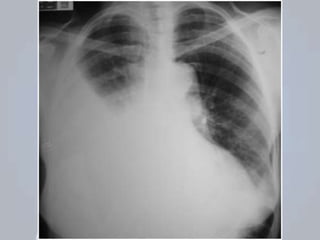

HEMOTÓRAX

 Presença de sangue no espaço pleural;

 Representa fonte de perda sanguínea importante;

 Mesmos mecanismos do pneumotórax;

Origem: parede da musculatura torácica, vasos

intercostais, parênquima pulmonar, vasos

pulmonares ou grandes vasos do tórax;

AVALIAÇÃO: desconforto; dor torácica e a dispneia;

Sinais de choque: taquicardia, taquipneia, confusão,

palidez e hipotensão.

EXAME FÍSICO: sons respiratórios são diminuídos

ou ausentes; percussão é abafada;

PNEUMOTÓRAX + HEMOTÓRAX: probabilidade de

comprometimento cardiorrespiratório;